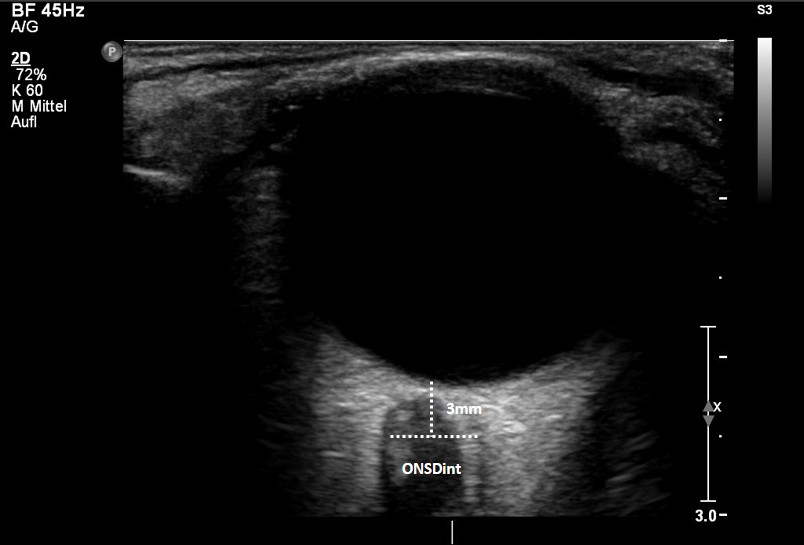

„Die Optikusnervenscheiden-Sonografie ist ein einfach anwendbares, nicht-invasives und hochrelevantes Verfahren, mit dem sich ein erhöhter Hirndruck frühzeitig feststellen lässt“, sagt Professor Dr. Michael Ertl, Leiter der Sektion Neurologie der DEGUM. „Unser Ziel ist, damit Diagnosen zu beschleunigen, unnötige Eingriffe zu vermeiden und die Prognose der Patientinnen und Patienten zu verbessern.“ Beim ONSD-Ultraschall wird ein passender Schallkopf sanft auf das geschlossene Augenlid aufgesetzt. Die Untersuchung macht sich zunutze, dass sich Veränderungen in der Regel an der Hülle des Sehnervs zeigen, wenn der Druck im Schädelinneren steigt. Für die Betroffenen bedeutet das: keine Strahlenbelastung, keine Schmerzen, kein Eingriff.

© DEGUM/Michael Ertl